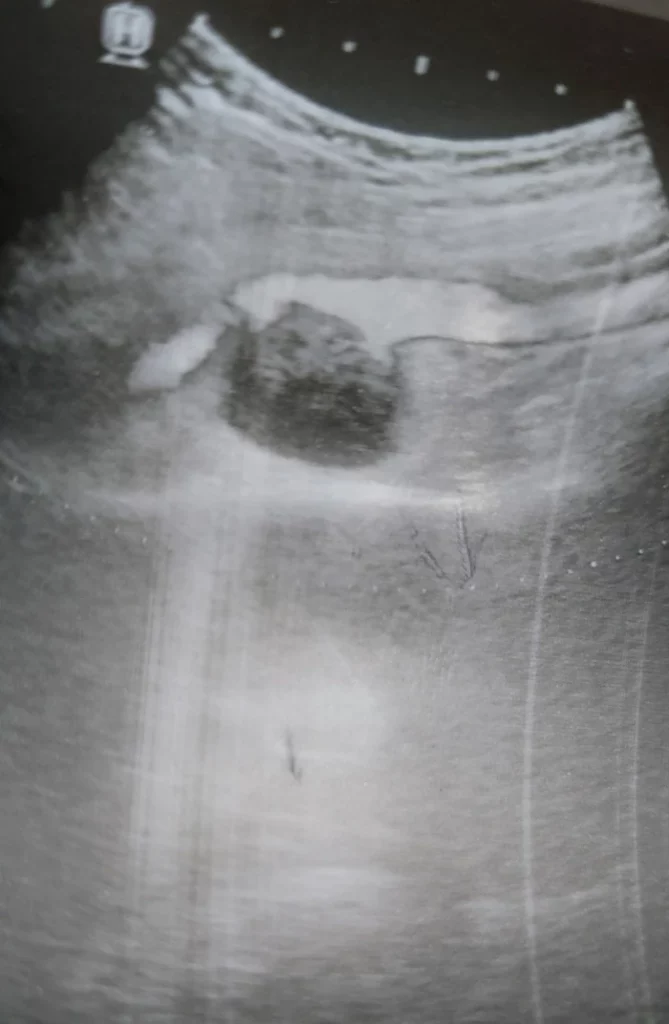

USG jamy brzusznej

To badanie jest nieinwazyjne i bezbolesne , wymaga przygotowania 6 godzin przed badaniem nie spożywamy posiłku, bez żucia gumy i palenia godzinę przed badaniem, podanie leku typu espumisan 4×2 dzień przed i w dniu badania. Oceniamy wątrobę, pęcherzyk żółciowy, trzustkę, nerki, śledzionę, pęcherz moczowy, prostatę u mężczyzn, drogi rodne u kobiet, aorta i główne naczynia, węzły chłonne. Wskazaniem jest badanie kontrolne, schodzenia lub podejrzenie choroby danych narządów, bóle.